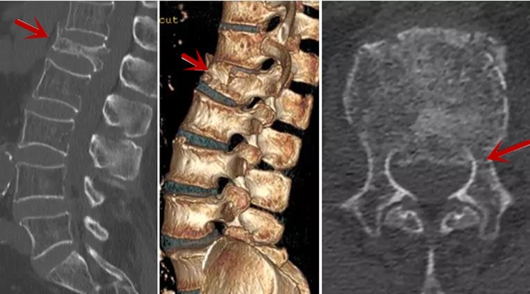

利器二:CT

CT利用X射線對(duì)人體檢查部位通過電腦切成若干層掃描,然后把每層的圖像都能顯示出來。CT相對(duì)于X光片具有更高的密度分辨力,可直接顯示X線片無法顯示的病變,觀察腰椎有無微小的骨折、骨質(zhì)有無破壞等骨質(zhì)情況、以及腰椎間盤突出、腰椎神經(jīng)根、椎管、椎間小關(guān)節(jié)的情況等。同時(shí)還可以通過后處理,重建腰椎矢狀位或冠狀位圖像,形成腰椎的3D圖像,更直觀地觀察病變部位,對(duì)腰椎手術(shù)風(fēng)險(xiǎn)具有提示作用,對(duì)手術(shù)方式的選擇具有指導(dǎo)意義,但是對(duì)神經(jīng)、脊髓損傷程度的顯示不如MRI,軟組織的分辨率仍有一定限制,對(duì)椎管內(nèi)病變顯示欠佳,且有一定的輻射。

箭頭提示椎間盤突出

從左向右依次為CT矢狀位重建圖像、三維重建圖像、軸位掃描圖像,箭頭提示腰1椎體爆裂性骨折